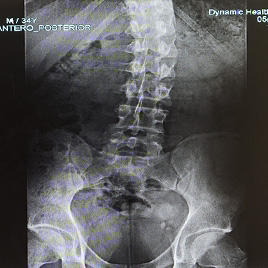

Using advanced diagnostics and proven treatment protocols, the medical professionals at Dynamic Health Carolinas take a multidisciplinary approach to relieving your discomfort.

Advanced Pain Diagnostics in Charlotte, NC